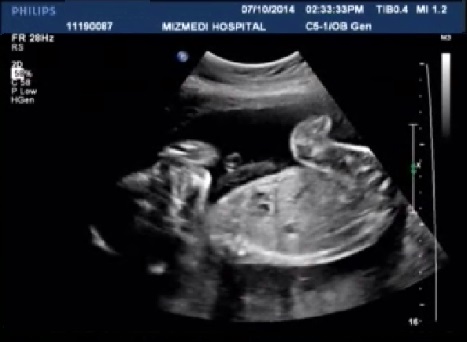

[태아초음파 동영상4] 미즈메디 중기 정밀초음파 동영상/ 초스피드로 끝난 중기 정밀 초음파

22주 5일 미즈메디 강서병원에서 중기 정말 초음파 했어요. 영상의학과에서 중기 정밀 초음파를 보...